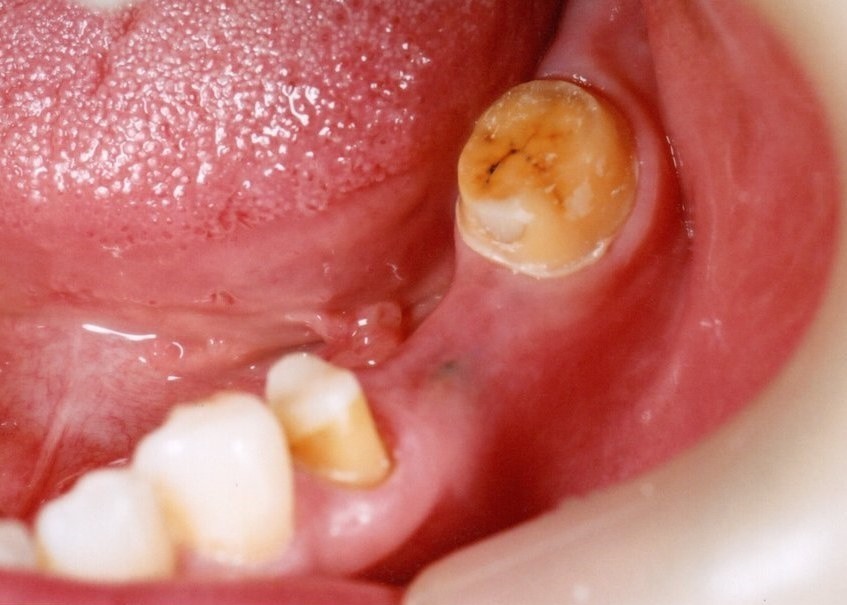

6本のインプラントで、12本の歯を並べる(下顎・仮歯代含む)

(裾野市在住 女性)

お口の中の状態

被せ物を外した状態

6本のインプラントを埋入し、12本の歯を並べています。第二大臼歯を作らない場合の理想的な治療法になります。

【下顎インプラント6本で12本の歯を回復するスクリュー固定タイプ】

インプラント手術:250,000円×6本=1,500,000円

静脈内鎮静法:0円

既製アバットメント:90,000円×6個=540,000円

メタルボンド:130,000円×12本=1,560,000円

マルチアバットメント:25,000円×6個=150,000円

連結料:10,000円×11カ所=110,000円

仮歯:50,000円×6本=300,000円

ポンティック:10,000円×6本=60,000円

ラジオグラフィックガイド(14本):23,000円

埋入ガイド(6本):73,000円

総額:4,316,000円+税